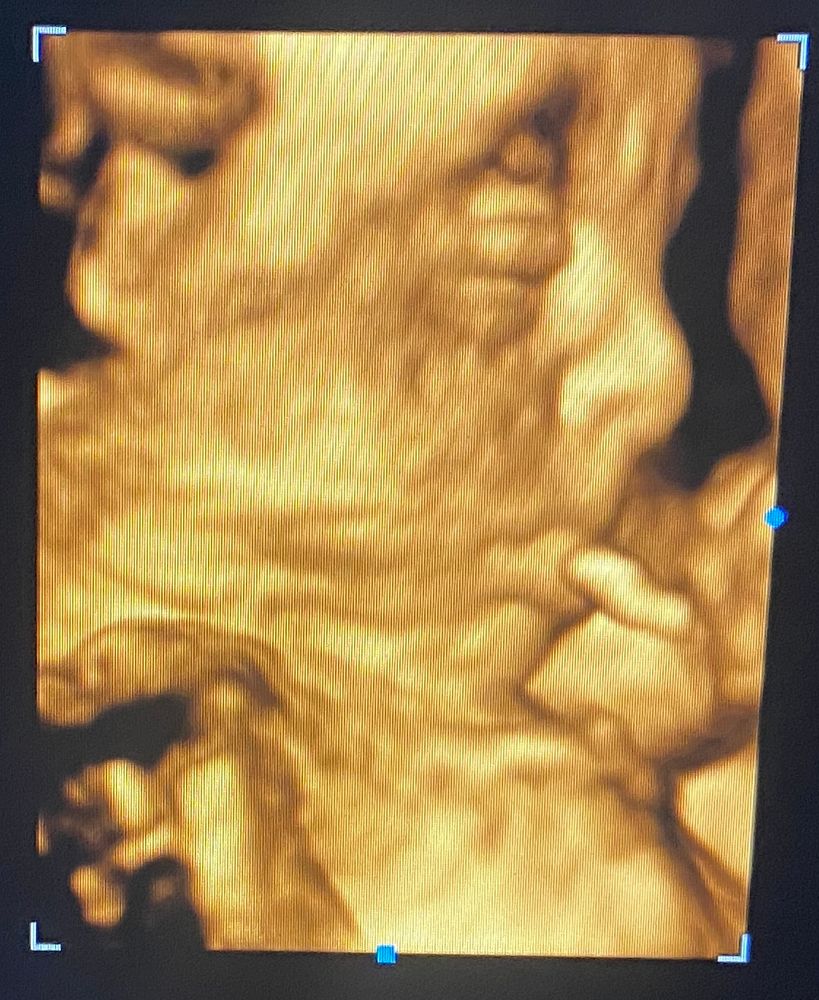

Делала ещё же узи в 25 недель ,на 2 скрине были увеличены боковые желудочки и сам желудок ,все уменьшилось 👌Носик так и остался кнопочным по замерам ,но это ерунда )

Весила она уже 744 гр 💓

Кое как сделали 3 д ,так как она лицом вниз и ещё руками закрывалась )